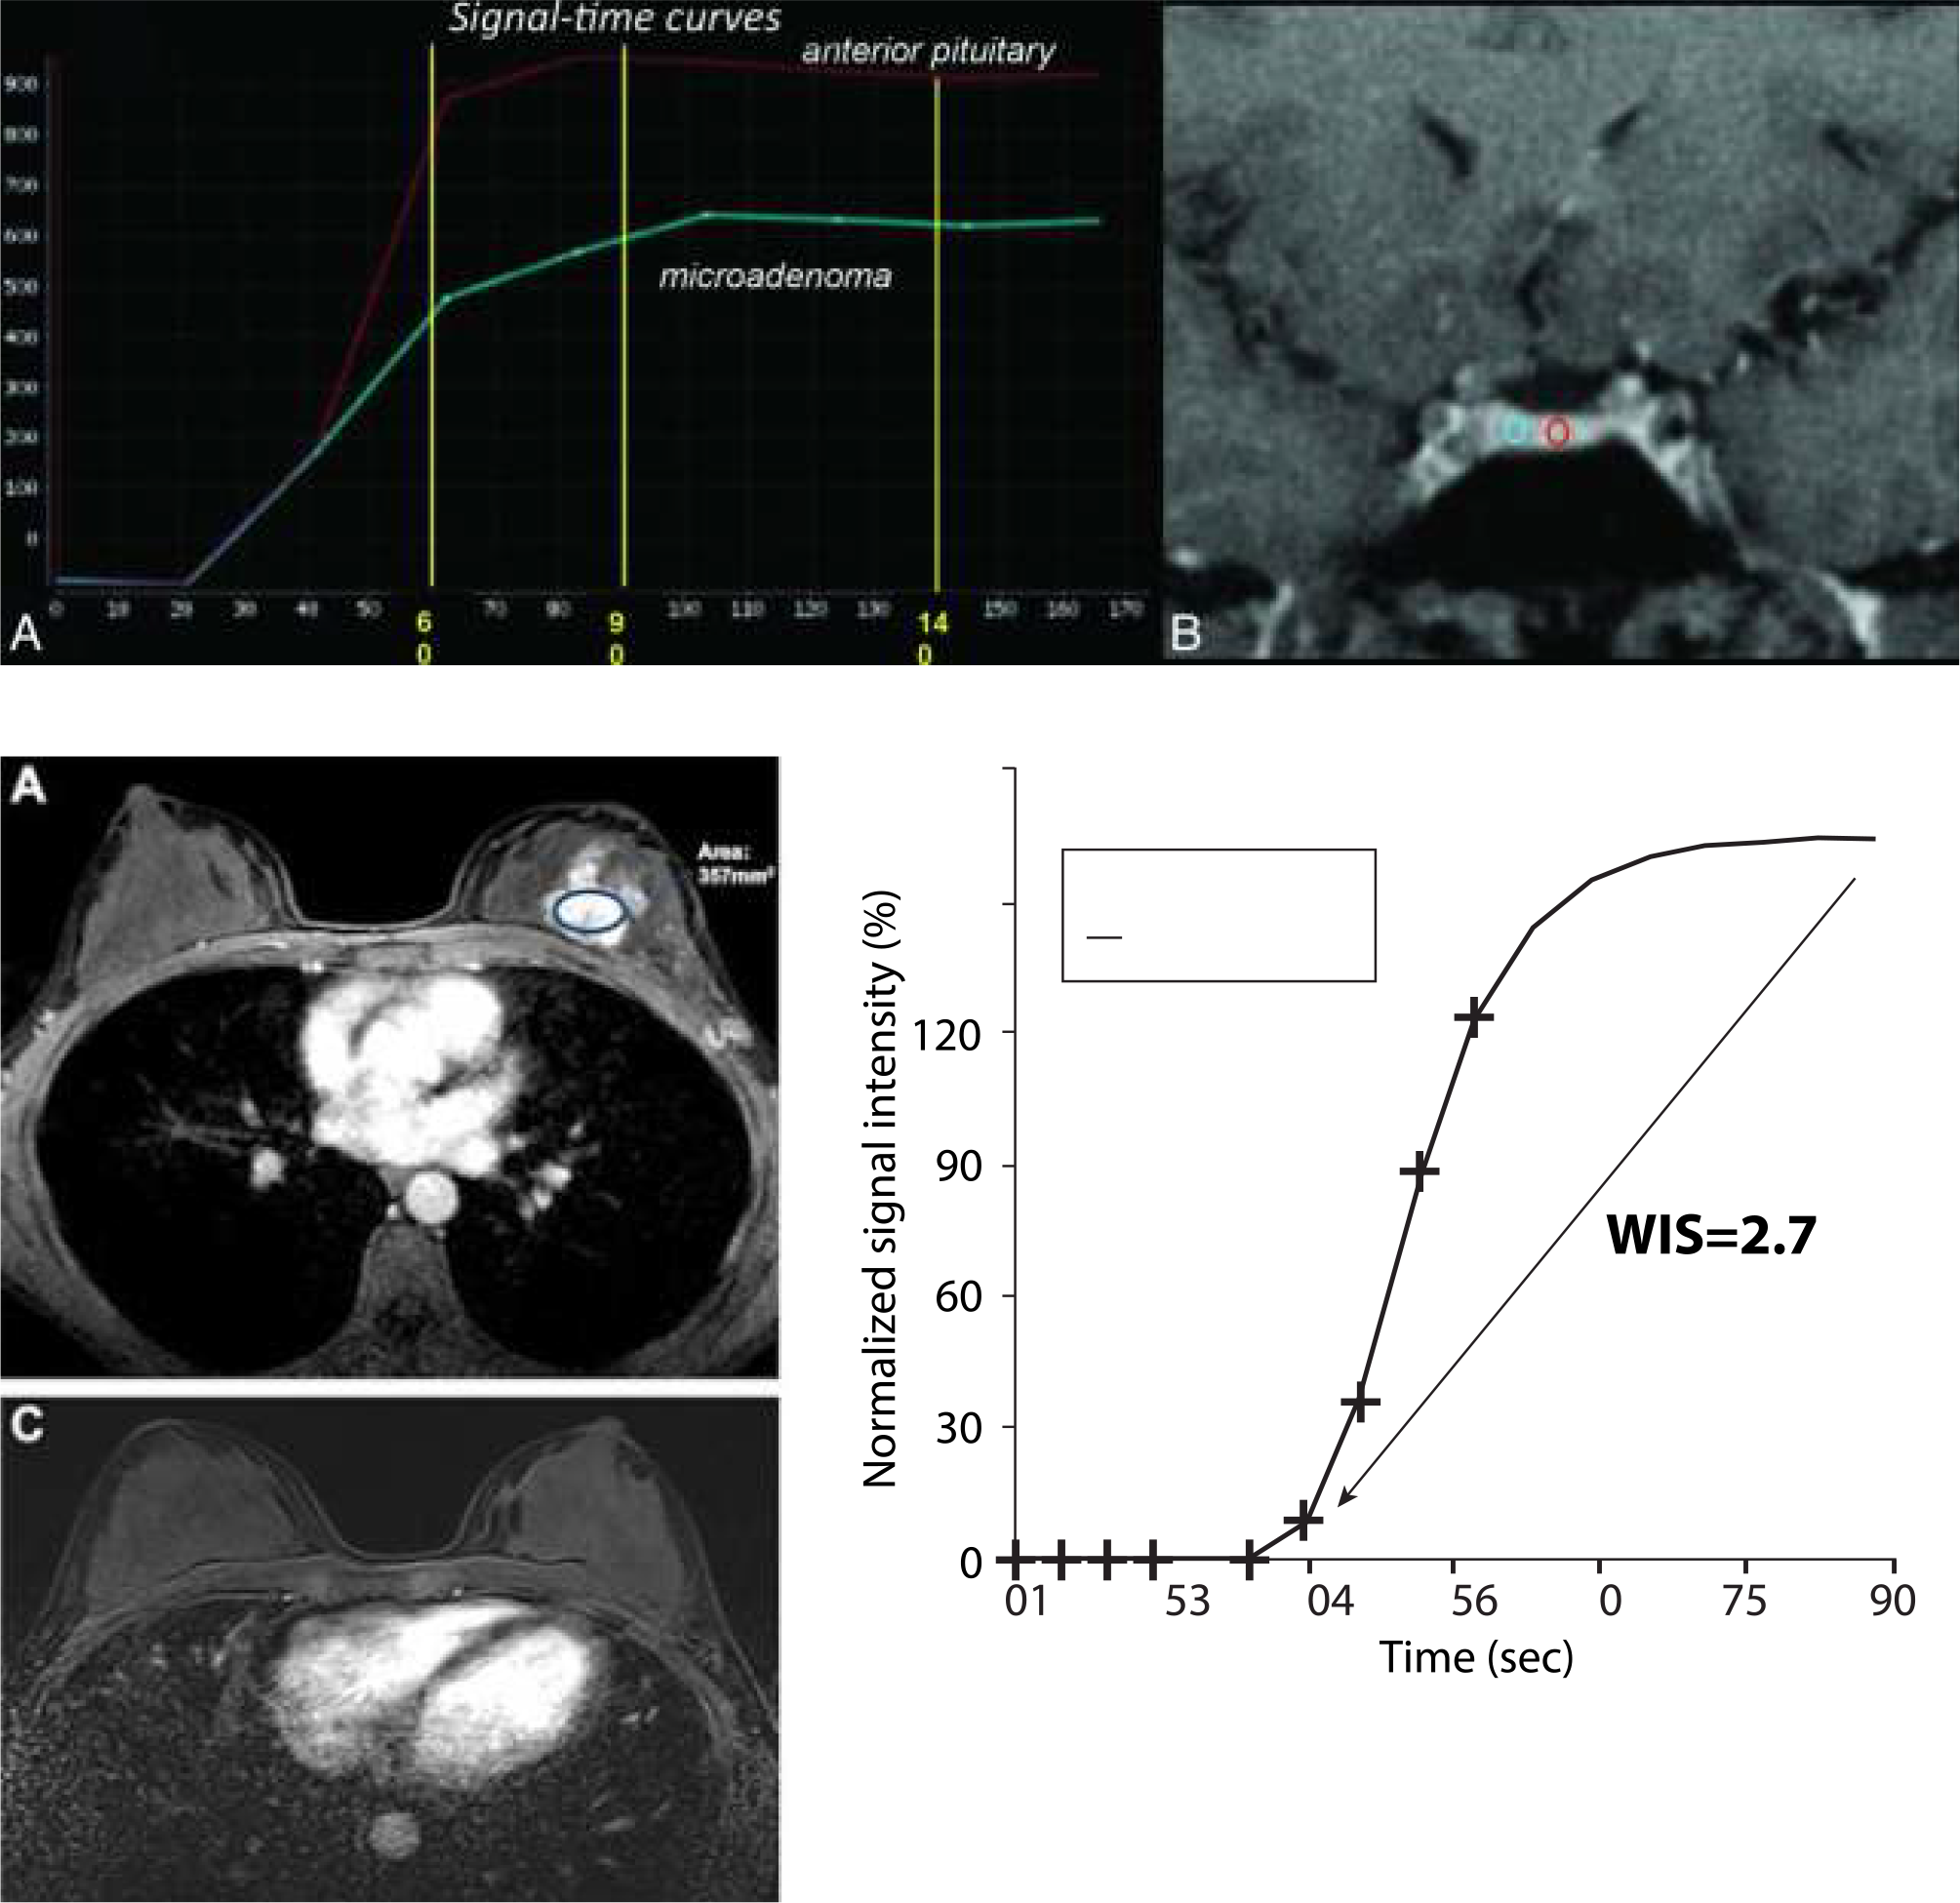

Clarity's high-quality imaging can be applied to a range of clinical neuro imaging.

MRA/MRV, DWI with multipe b-value, ADC and eADC, SWAPP (SWI), Tornado (motion correction), ASL, DTI, Single Voxel Spectroscopy, DCE - MRI